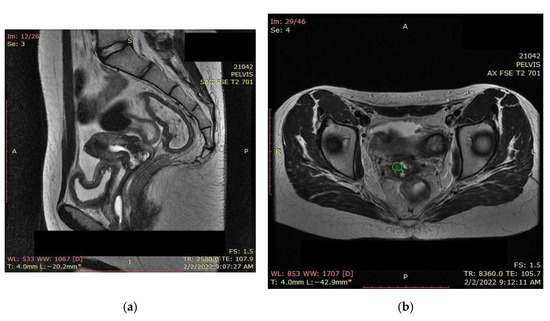

An MRI scan performed immediately the next day after finishing the radiotherapy and chemotherapy sessions showed a significant favorable response, with the persistence of a necrotic and ulcerative cervical area and a possible residual lesion on the right side of the cervix (Figure 12).

Due to the persistent residual tumor after radiotherapy and chemotherapy (Figure 13), the patient was referred for intracavitary brachytherapy, achieving favorable evolution and almost complete response (Figure 14). She underwent three sessions of 3D intracavitary and interstitial cervico-uterine brachytherapy, after the insertion of 8 needles Ring and Tandem applicator. All three sessions took place 2 days apart in December 2021, the first one with 7.5 Gy, and the next two with 8 Gy.

Figure 13. (a) MRI and (b) CT—significant favorable post-radiotherapy and chemotherapy response, with the persistence of a necrotic and ulcerative cervical area and a possible residual lesion on the right side of the cervix (the green highlighted area).